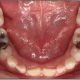

متداولترین مواد در ساخت روکشهای دندانی پرسلن و رزین کامپوزیت و همچنین سرامیک است. هنگامی که این مواد توسط یک دندانپزشک زیبایی باتجربه استفاده میشود، هر یک از این سه ماده میتواند لبخند شما را زیباتر کرده و آن را به یک لبخندی که شایسته یک سوپراستار است تبدیل کند. با این حال، کدام نوع روکش مناسب شماست؟

اگرچه روکشهای دندانی رزینی و کامپوزیت سرامیکی دارای چندین ویژگی و فواید هستند، اما در زمینه دوام نمیتوانند با پرسلن رقابت کنند. با این که روکشهای دندانی سرامیکی شاید کمی قابل تنظیمتر از پرسلن یا کامپوزیت باشد، اما از نظر سختی با پرسلن قابل تعویض است. به هر حال، پیش از چسباندن روکشهای چینی (پرسلن) واقعی که 100 در 100 درصد از چینی ساخته شدهاند برای زیبایی نیاز است که دندانها را کانتور کنید.

روکشهای دندانی رزین

مواد کامپوزیت رزین فقط مادهای نیست که برای پر کردن دندان مورد استفاده قرار میگیرد، آنها همچنین میتوانند برای روکشها استفاده شوند. آنها بسیار دوام کمتری نسبت به همتایهای چینی و سرامیکی خود دارند. آنها همچنین از هر دو ماده متخلخلتر هستند و این باعث میشود در برابر لکهدار شدن آسیبپذیر شوند. با این حال، ترمیم مستقیم روکشهای دندانی رزین گزینهای برای بسیاری از افراد است زیرا به اندازه کافی خوب است و برای 5 تا 7 سال، که متوسط طول عمر روکش است، دوام میآورد.